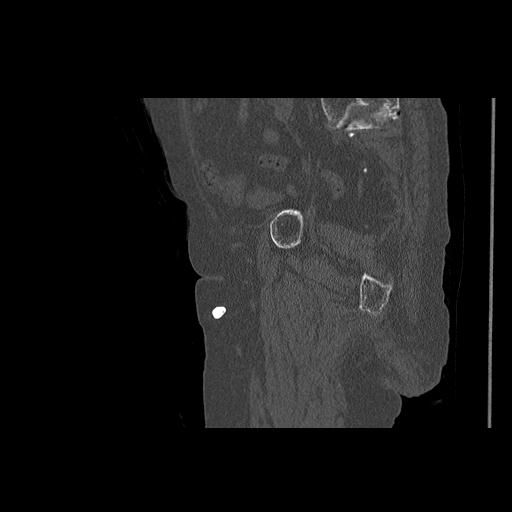

100703 1/27 両股正面+軸 1/29 両股正面+軸 94歳女性 パンソンロン